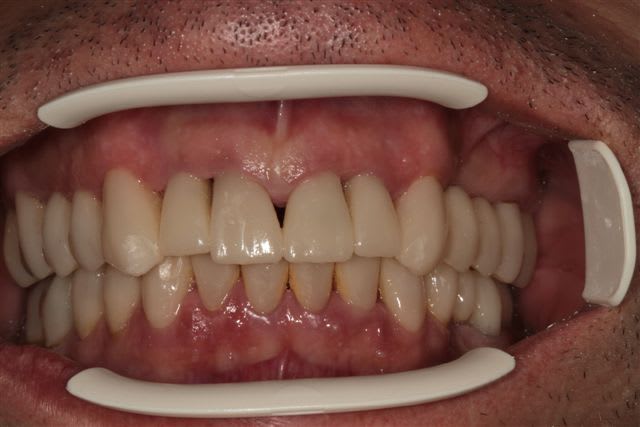

N'étant pas spécialiste de la paro, voici un cas ou je ne sais quoi faire de plus!

Patient 50 ans, gros fumeur, lithotricié à Nice, n'a semble t il jamais eu de prise en charge globale.

Les photos de départ